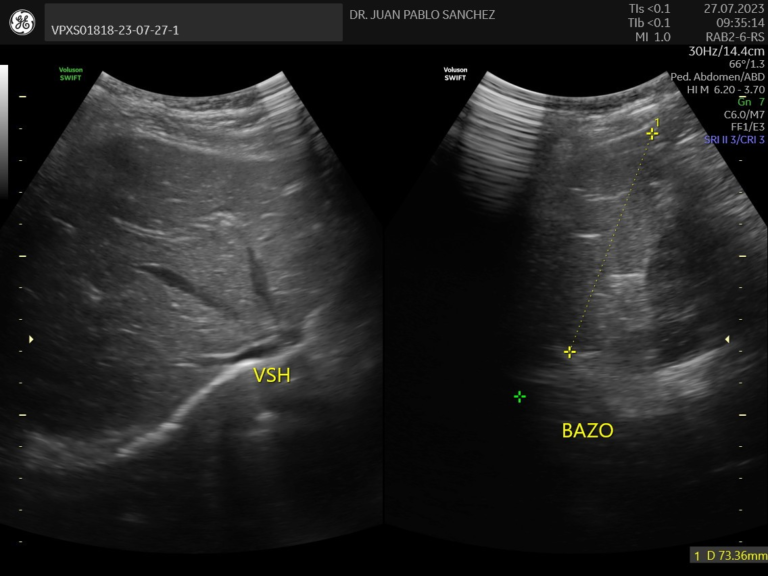

Ecografia abdominal

Estudio no invasivo que permite observar los órganos del abdomen, como el hígado, riñones, intestinos, vejiga, etc. Es útil para detectar infecciones, malformaciones o dolores sin usar radiación ni dolor.